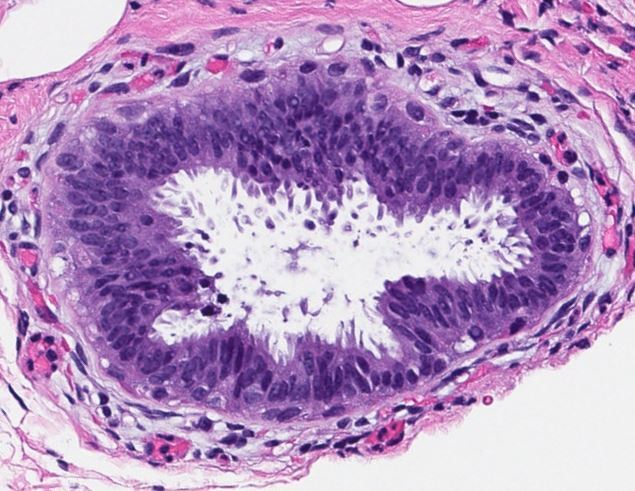

Taken from a male patient

Gynecomastia

Contains fibrous stroma and branching ducts with terminal ductules, but extremely few (if any) acini. In early stages, there is a loose periductal stroma with a mixed chronic inflammatory infiltrate, extensive epithelial hyperplasia, and tapering tufts (pyramid-shaped micropapillae). In later stages, there is fibrosis and hyalinization of periductal stroma and epithelial atrophy.

Here, early stage gynecomastia is shown.

Benign lesion of the male breast, often bilateral. Caused by androgen/estrogen imbalance. Physiologic in children, but often pathogenic in adults. May be seen normally during puberty, or in those taking dopaminergic medications, hormone therapy, those with Klinefelter syndrome, cirrhosis, or obesity.

No associated risk of malignancy.